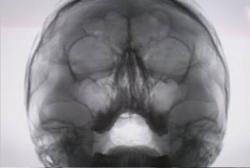

Протокол. На обзорной цифровой флюорограмме придаточных полостей носа (1) справа в гайморовой полости определяется каплевидной формы образование малой интенсивности, с четкими, ровными контурами, однородной структуры. Данное образование шейкой (тонкой ножкой) связано с верхней стенкой гайморовой полости. При обработке изображения в режиме «эквилизация» и с увеличением в 1,5 раза (2) – в условиях позитива и в 2,0 раза в условиях негатива (3) тень полипоподобного образования видна более отчетливо и структурно, намечается неоднородность тени.

1. Обзорная цифровая флюорограмма придаточных полостей носа

2. Режим «эквилизация» и с увеличением в 1,5 раза в условиях позитива

3. Режим «эквилизация» и с увеличением в 1,5 раза в условиях негатива